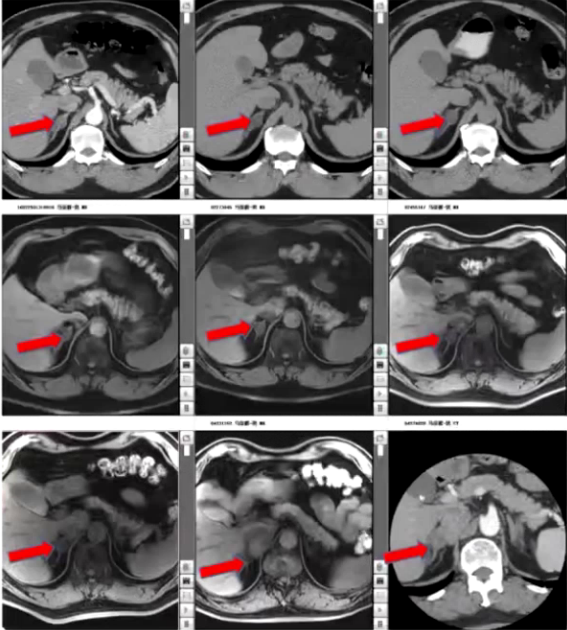

1) 基本情况:患者为67岁老年男性,因血压升高30年,右肾上腺旁占位进行性增大8年入院。30年前无明显诱因出现头晕伴恶心,测血压升高,开始口服复方降压片,血压控制尚可。13年前坐车时突发头晕头痛,测血压190/100mmHg,胸部CT检查发现右侧肾上腺内侧肢及结合部低密度影,考虑腺瘤可能。

2) 入院前检查:2010年11月血钾4mmol/L,卧位肾素活性0.25ng/mL/h,醛固酮107pg/mL,立位肾素活性1.1ng/mL/h,醛固酮141pg/mL,卡托普利试验未被抑制,去甲肾上腺素0.682pmol/mL,肾上腺素0.03pmol/mL,多巴胺0.121pmol/mL,24小时尿香草苦杏仁酸(VMA)19.6mg。腹部增强CT提示双侧肾上腺结节影,多发腺瘤,右侧1.6cm×0.9cm,左侧0.8cm×0.8cm,不除外合并双侧肾上腺增生。垂体MRI未见异常,考虑原发性醛固酮增多症可能性大。因双侧肾上腺腺瘤,行双侧肾上腺静脉取血术,考虑采血并不在位,患者要求保守治疗,予硝苯地平控释片、螺内酯、氯沙坦钾控制血压,后调整降压方案为硝苯地平控释片、螺内酯、酒石酸美托洛尔片,血压控制在130/70mmHg左右。此后定期复查影像检查,双侧肾上腺腺瘤变化不大。

3) 病情转折:入院前两个月,患者自觉偶有头痛,夜尿增多,近半年体重下降10kg。2023年10月17日复查,肾素水平119.6pg/mL,醛固酮65.3ng/dL,24小时尿香草扁桃酸(VMA)14.45mg/24h,较起病初期明显增高。肾上腺MRI显示双侧肾上腺多发结节,较前变化不明显,胆囊结石较前增大,右侧膈肌脚旁肿块4.3cm×2.6cm较前增大。患者以“肾上腺占位及膈肌脚旁占位”收入院。

1) 病因探寻:患者此次血压波动,既往原发性醛固酮增多症诊断明确。血儿茶酚胺提示甲氧基去甲肾上腺素2026.6pmol/L、甲氧基肾上腺素792.6pmol/L,均超过参考范围。肾上腺CT提示右侧肾上腺内侧下腔静脉与右侧膈肌之间肿块影4.3cm×2.6cm,考虑神经源性肿瘤,原有双侧肾上腺多发腺瘤仍存在。PET-CT检查提示双侧肾上腺多发低密度结节,部分代谢活性增高,为功能性腺瘤,右侧膈肌角旁代谢活性增高的软组织密度肿块性质待定,不完全除外低度恶性肿瘤可能。结合患者右侧膈肌脚旁占位逐年增大、体重减轻、周围循环充盈欠佳、体位性低血压、血尿儿茶酚胺指标升高,考虑副神经节瘤为此次病情变化主要原因。